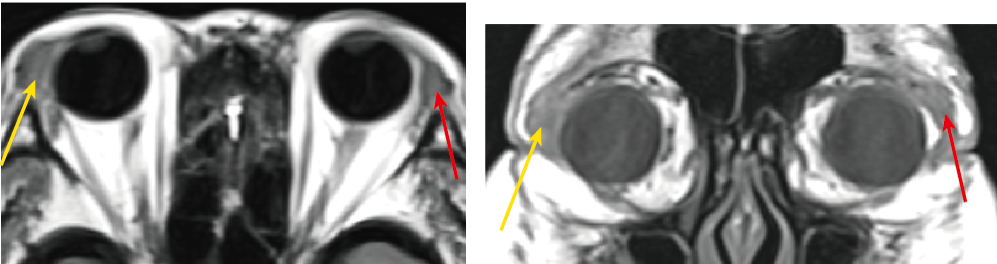

さらに術後に撮像したMRIでは、手術で一部切除した左の涙腺部病変は縮小していましたが(図の赤矢印)、右の涙腺は著明に腫大(図黄矢印)していました。